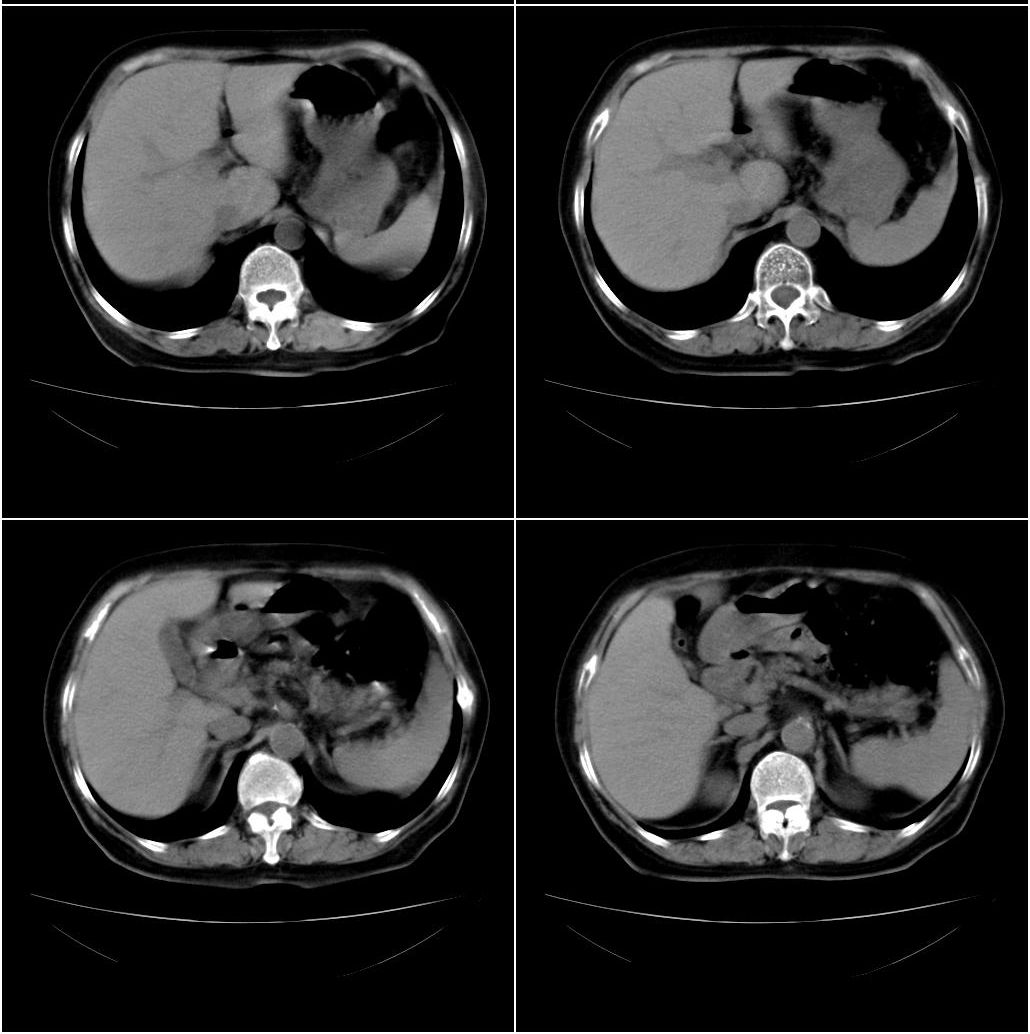

以下是引用sxlcbc在2007-12-23 4:27:00的发言:[br]气管源性肿瘤觉得有点不靠谱啊,看上去气管是受压改变的。更像是上段食管的改变,周围淋巴结肿大,食管受压。看看以下六幅图片:[br]不过,有一点不好理解:食管肿瘤应该有食道症状的,再说食管癌出现周围这么大的淋巴结也不多见啊,如果考虑淋巴瘤倒是更合理一点,这样气管,食管受压改变也许更合理一些。[br][br]